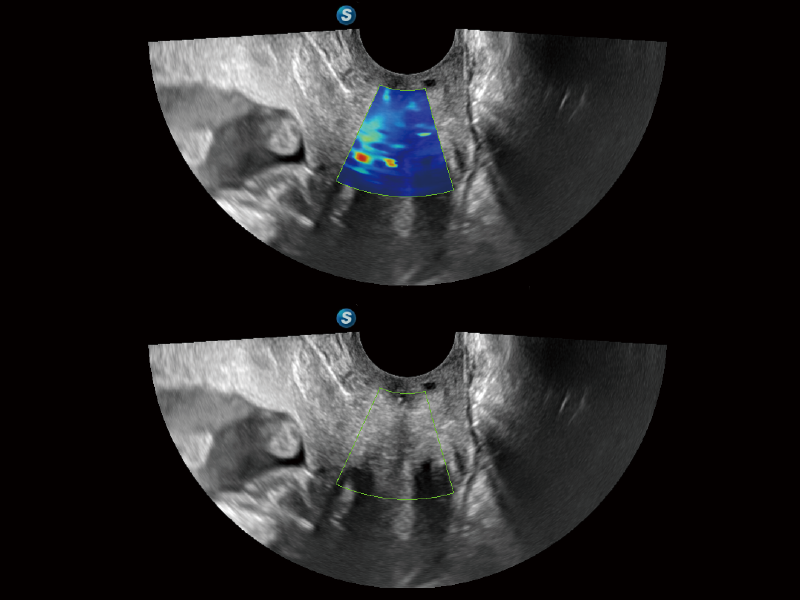

Fine-tuned Hemodynamic Solution

A wide variety of hemodynamic diagnostic techniques enable effective blood flow signal detection across different scenarios.

• FHR

FHR enables the observation of microvascular structure within organs with enhanced sensitivity and improved resolution, ensuring the precision in representing the actual state of blood circulation.

• Bright Flow

Bright Flow offers 3D-like color Doppler flow visualization without requiring a volume transducer, thereby strengthening the boundary definition of vessel walls.

• Micro F

Micro F efficiently distinguishes subtle blood flow signals from overlaying tissue motion, enabling heightened sensitivity and spatial resolution in hemodynamic depiction.